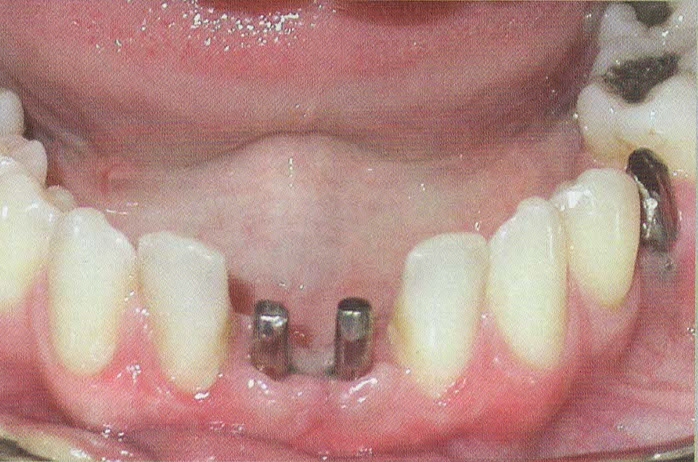

CERAMICHE SU IMPIANTI

Per l'esecuzione delle impronte vengono usati materiali di prima qualità perchè la precisione delle impronte facilita la costruzione del manufatto e questo è un passaggio fondamentale per la buona riuscita della protesi.

In questo studio vengono eseguite ceramiche di ultima generazione quali la zirconia ceramizzata, le ceramiche estetiche in disilicato senza trascurare le tradizionali metalceramiche. Il disilicato è un materiale altamente estestico che conferisce alla corona protesica un aspetto naturale e con questo materiale si possono creare manufatti con uno spessore molto ridotto.